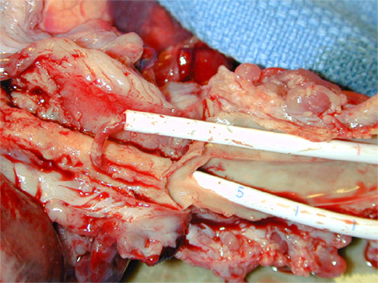

Tunnelierung und Port

Langzeitkatheter und Portkatheter werden von der Punktionsstelle supraklavikulär 4 - 6 cm bis zum Thorax tunneliert.

Da tunnelierte Katheter eine fixe Länge haben, muß die Austrittsstelle exakt vermessen werden, dass einerseits die Katheterspitze im Vorhof bzw. der Vena cava superior liegt, andererseits der Tefloncuff mindestens 2 cm von der Austrittsstelle entfernt im Tunnel.

Portkammern sollen im Trigonum deltoideo-pectorale (Mohrenheim´sche Grube) liegen, bei Frauen ist darauf zu achten, dass sie nicht unter dem BH-Träger liegen und keinesfalls auf dem Brustansatz.

Die weiblich Brust hat die Eigenschaft, im Stehen der Schwerkraft zu folgen, und zwar umso mehr, je schwerer die Brust und je älter die Patientin. Der Port wandert dann mit der Brust nach unten und disloziert den Katheter aus der Vene. An den erweiterten Venen am linken Oberarm und Thorax erkennt man auch eine weitere Komplikation: die Thrombose der Vena subclavia.

Im Röntgen sieht man den dislozierten Katheter und die Kontrastmittelextravasation ins Mediastinum. Dorthin wurde auch das hochgradig gewebetoxische Adriamycin infundiert.